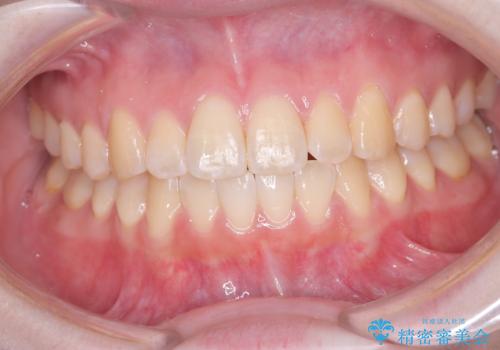

インビザライン矯正 前歯のガタツキが治り、綺麗なスマイルに!